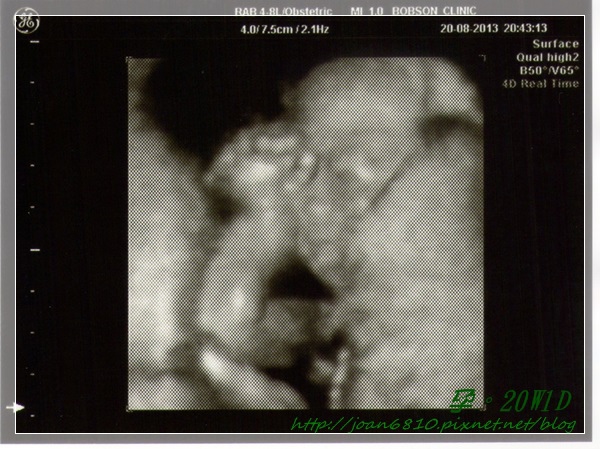

• 【孕。二寶】20W1D

20W002.jpg

20W1D產檢

又一個月過去了~又要來交待一下目前狀況